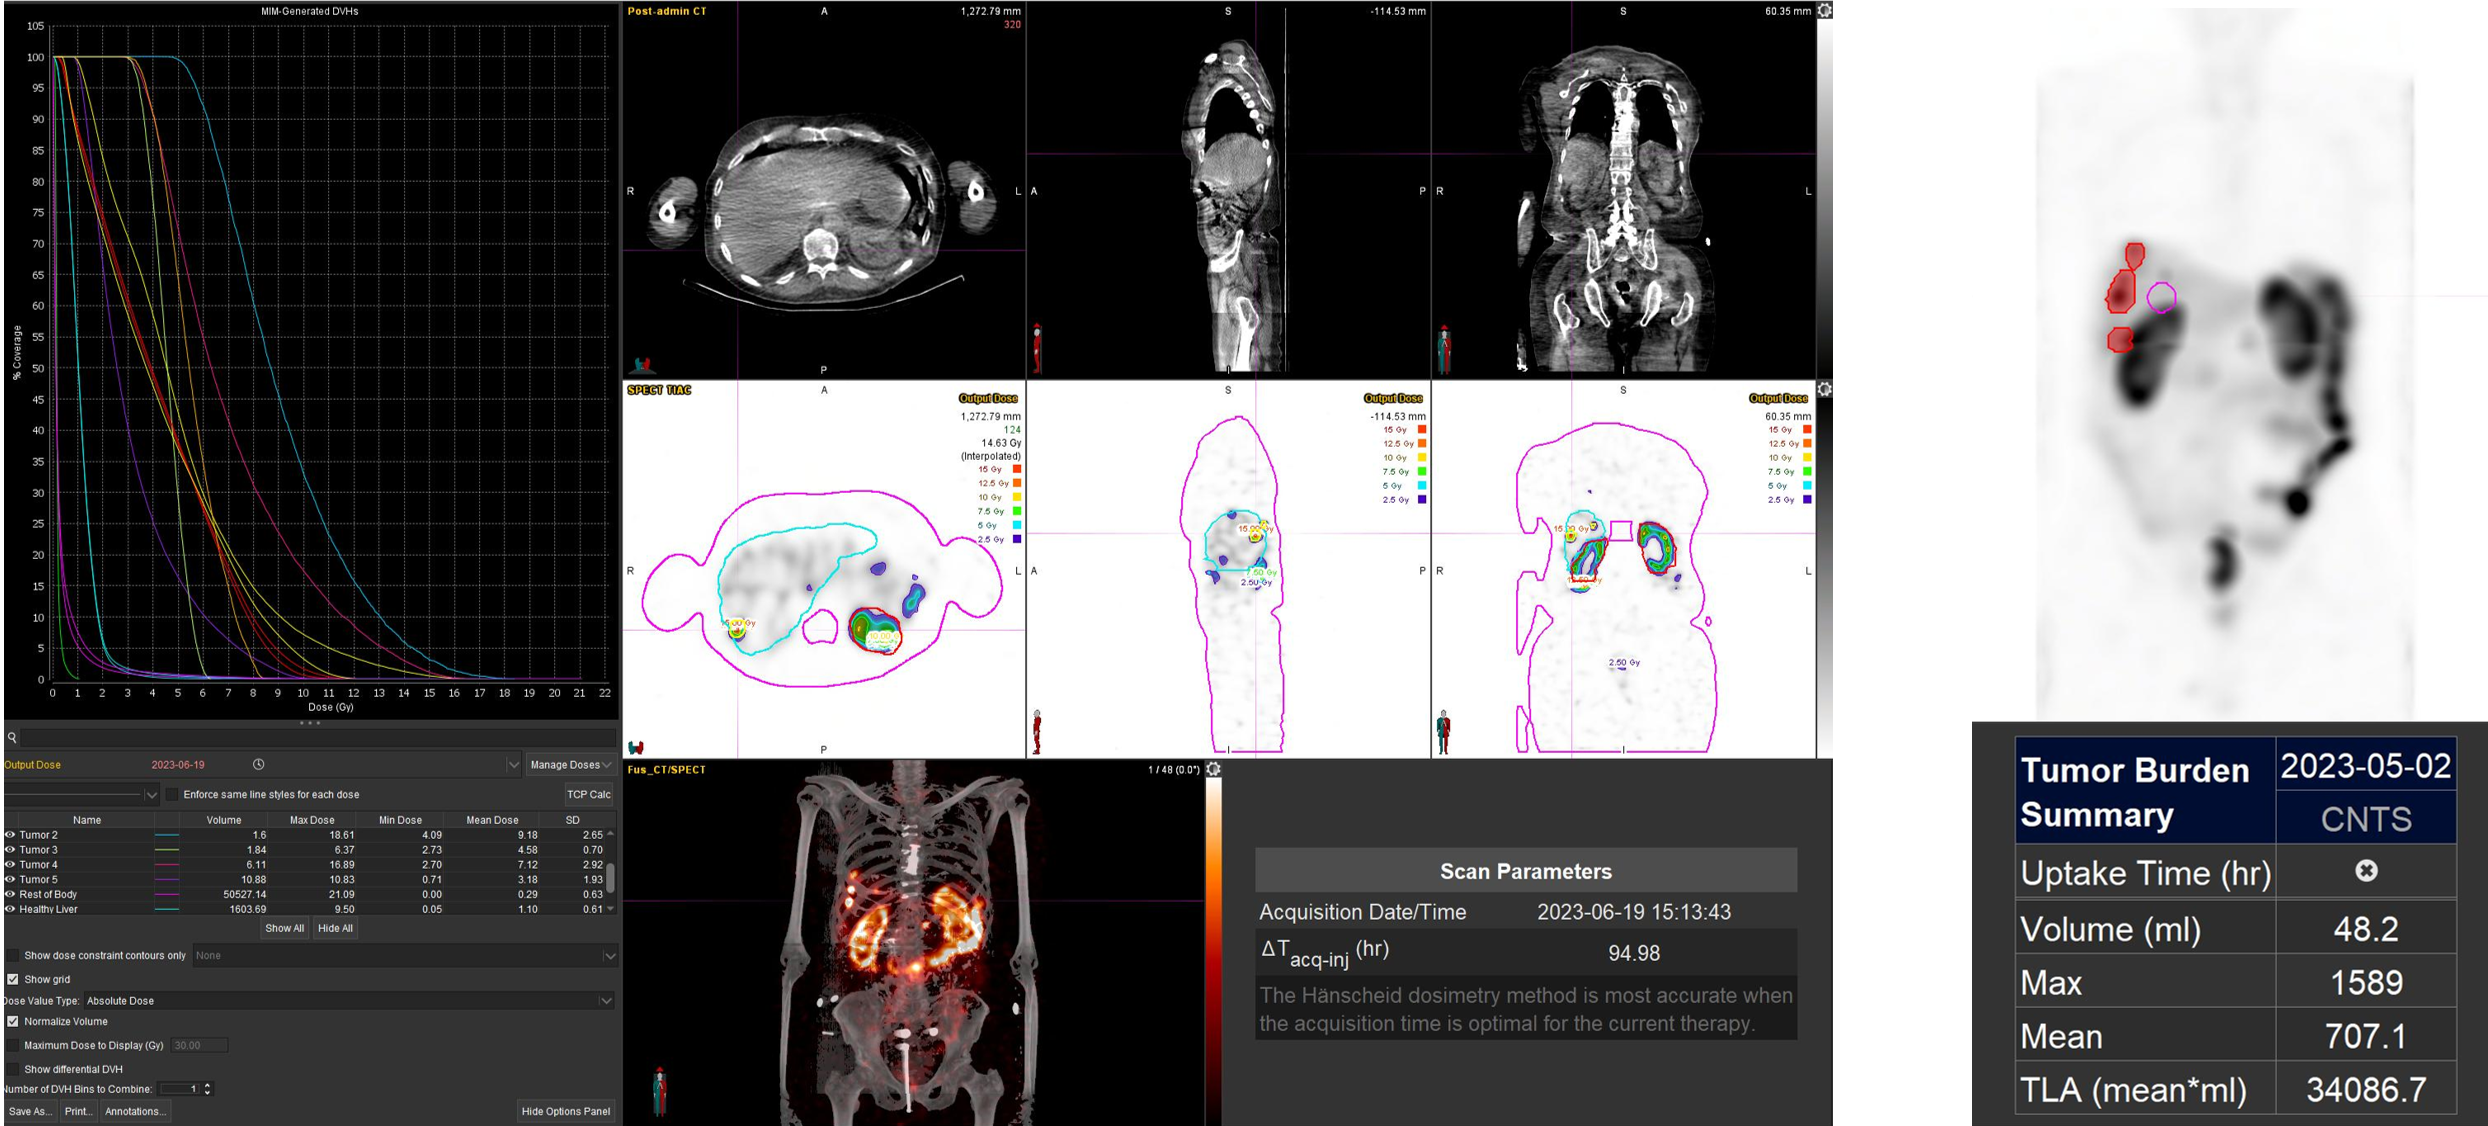

Η θεραπεία με Ύτριο-90 SIR-Spheres (Y-90) αποτελεί μια εξειδικευμένη τεχνική εκλεκτικού ενδοαρτηριακού εμβολισμού, η οποία στοχεύει αποκλειστικά τον όγκο μέσω των ηπατικών αγγείων, επιτρέποντας την εναπόθεση σωματιδίων που εκπέμπουν ραδιενέργεια τοπικά με ελάχιστη ακτινική επιβάρυνση στους υγιείς ιστούς. Η διαδικασία περιλαμβάνει λεπτομερή προθεραπευτικό αγγειογραφικό σχεδιασμό με αξιολόγηση της αγγειακής ανατομίας και χορήγηση ενός ιχνηθέτη για την ανίχνευση τυχόν διαφυγής (πχ. lung shunt), εξασφαλίζοντας μέγιστη ασφάλεια και εξατομίκευση. Η επιλογή της δόσης γίνεται πλέον με σύγχρονα υπολογιστικά μοντέλα δοσιμετρίας και εξειδικευμένα λογισμικά (όπως MIM ή SIR-TeX platform), τα οποία επιτρέπουν ακριβή αποτύπωση του όγκου της νόσου στο ήπαρ, υπολογισμό του πραγματικού tumor burden και εκτίμηση της απορροφούμενης δόσης τόσο στον όγκο όσο και στο υγιές ηπατικό παρέγχυμα. Μετά τη θεραπεία, πραγματοποιείται έλεγχος κατανομής της ακτινοβολίας (μέσω Bremsstrahlung SPECT/CT ή PET/CT), ενώ ακολουθεί στενή απεικονιστική και κλινική παρακολούθηση για την αξιολόγηση της ανταπόκρισης, την εκτίμηση τυχόν τοξικοτήτων και τον σχεδιασμό επόμενων βημάτων στην ογκολογική στρατηγική του ασθενούς. Πρόκειται για μια ιδιαίτερα αποτελεσματική θεραπευτική επιλογή σε πρωτοπαθείς ηπατικούς όγκους και σε ηπατικές μεταστάσεις, ειδικά όταν οι συμβατικές θεραπείες έχουν περιορισμένη αποτελεσματικότητα ή δεν είναι πλέον εφικτές.

Η θεραπεία με Lu-177 DOTATATE (PRRT – Peptide Receptor Radionuclide Therapy) αποτελεί μια από τις πλέον εξελιγμένες μορφές στοχευμένης ραδιονουκλιδικής θεραπείας για νευροενδοκρινείς όγκους του γαστρεντερικού και του παγκρέατος, αξιοποιώντας την υπερέκφραση των υποδοχέων σωματοστατίνης στους νεοπλασματικούς ιστούς. Η διαδικασία περιλαμβάνει τον ακριβή προσδιορισμό της έκτασης της νόσου μέσω Ga68 DOTATATE PET/CT, την επιβεβαίωση υψηλής έκφρασης υποδοχέων SSTR και στη συνέχεια τη χορήγηση του Λουτέσιο-177 DOTATATE, το οποίο δεσμεύεται εκλεκτικά στους ανωτέρω υποδοχείς. Η ενέργεια του β-εκπομπού Λουτέσιου επιτρέπει στοχευμένη κυτταροτοξική δράση μέσα στον όγκο, με ελάχιστη διασπορά σε υγιείς ιστούς. Η σύγχρονη πρακτική ενσωματώνει ειδικά λογισμικά δοσιμετρίας, που υπολογίζουν την απορροφούμενη δόση σε κρίσιμα όργανα (ήπαρ, νεφροί, μυελός) και την πραγματική δόση στον όγκο, επιτρέποντας εξατομικευμένο σχεδιασμό και βελτιστοποιημένη θεραπευτική στρατηγική. Μετά από κάθε κύκλο θεραπείας πραγματοποιείται απεικονιστικός έλεγχος, αξιολόγηση τοξικοτήτων και συνολική εκτίμηση ανταπόκρισης, καθοδηγώντας τις επόμενες φάσεις της θεραπείας. Το Lu-177 DOTATATE έχει αποδειχθεί εξαιρετικά αποτελεσματικό στη σταθεροποίηση και συχνά στη συρρίκνωση της νόσου, παρατείνοντας την επιβίωση και βελτιώνοντας σημαντικά την ποιότητα ζωής των ασθενών.

Η αξία της μεταθεραπευτικής δοσιμετρίας

Με τη SPECT‑CT ποσοτικοποίηση υπολογίζουμε απορροφούμενες δόσεις σε όγκους και όργανα‑στόχους (νεφροί, σιελογόνοι, ήπαρ, μυελός κ.ά.). Αυτό:

Σημείωση: Σύμφωνα με πρόσφατες κλινικές εργασίες/σειρές ασθενών – όπως οι LUMEN‑2 (για ΝΕΤ) και νεότερες μελέτες σε PSMA‑στόχο – η ποσοτική δοσιμετρία συσχετίζεται με την έκβαση και βελτιώνει τον θεραπευτικό σχεδιασμό.

Με βάση τα σύγχρονα Guidelines όλων των διεθνών ογκολογικών εταιρειών η μεταθεραπευτική απεικόνιση είναι προαπαιτούμενο για την έναρξη-συνέχιση της θεραπείας και το βέλτιστο αποτέλεσμα αυτής.

ΠΟΣΟΤΙΚΗ ΕΚΤΙΜΗΣΗ – ΜΕΤΡΗΣΗ ΟΓΚΟΥ ΝΟΣΟΥ